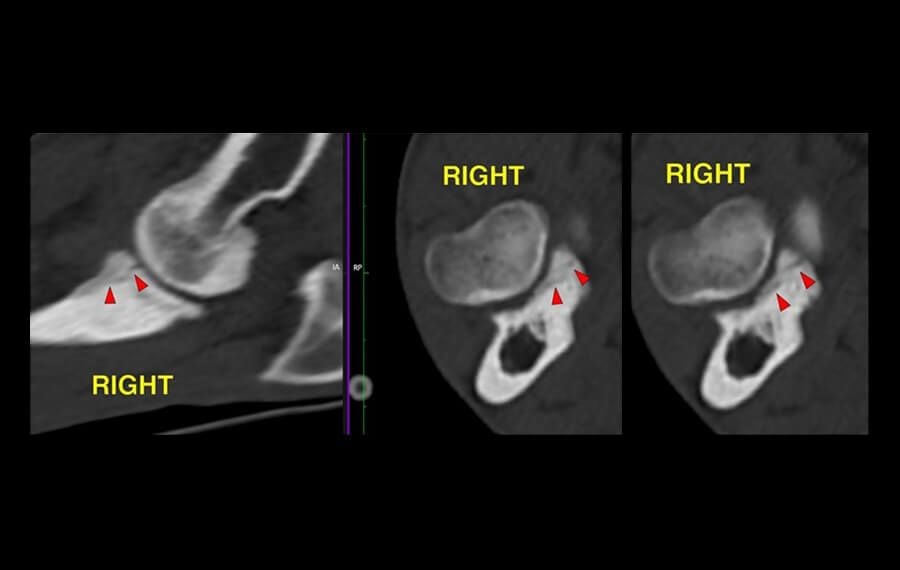

Precision Diagnosis: The Power of CT

X-rays often struggle to capture the fine details of the elbow joint. At VSOS, we utilise high-resolution CT Scanning as our gold standard for diagnosis.

A CT scan allows us to see the joint in 3D, identifying tiny cracks, bone fragments, or subtle misalignments (incongruity) that are invisible on standard X-rays. This precision allows our specialists to plan the exact surgical intervention required for your pet's unique anatomy.